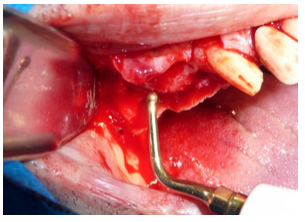

Para o acesso à cavidade sinusal se faz uso de ponta piezocirúrgica esférica, diamantada (figura 4). O aparelho utilizado foi um Piezosonic Driller ®. A demora na osteomia na osteotomia é compensada pela precisão e na proteção à membrana sinusal.